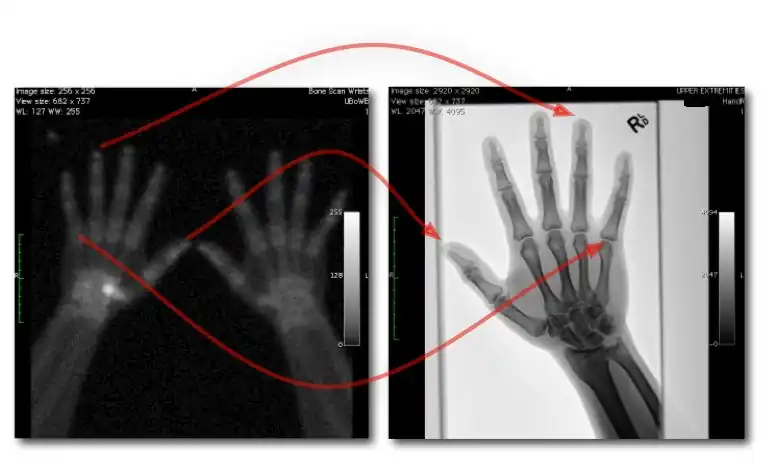

![]() |

- Examples of image display manipulation are shown in the two figures above. In Figure 7.15.2, the same image of a slice through a patient's liver is displayed using a relatively narrow window (high contrast) and also with a wide window. The image with the narrower window appears noisier, but this is merely a reflection of the fact that the gray scale is spread over a narrow range of CT-numbers.

- Figure 7.15.3 illustrates the use of a relatively narrow window to highlight pathology in the lungs.